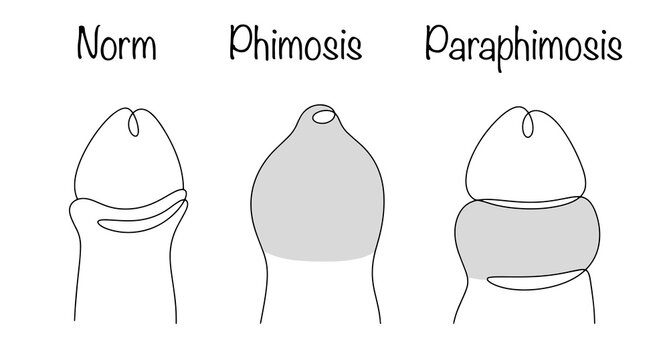

Phimosis (Conventional & Stapler)

Safe and effective surgical treatment of phimosis using both conventional and stapler techniques. Procedures are quick, minimally invasive, and patient-friendly. Ensures faster recovery and improved hygiene.